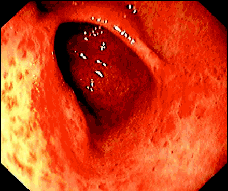

Endoscópicamente se reconocen dos formas: 1) longitudinal, que forma columnas eritematosas orientadas sobre los pliegues del antro (Figuras 1) y 2) difusa con múltiples lesiones rojizas puntiformes distribuidas de manera no uniforme en el antro (Figura 2). La forma difusa predomina en los pacientes cirróticos mientras que la longitudinal es más frecuente en los no cirróticos. El diagnóstico endoscópico de GAVE puede ser sumamente difícil por lo que se aconsejan las biopsias. La histología típica muestra ectasia capilar con trombos de fibrina e hiperplasia fibromuscular en la lámina propia.

El diagnóstico diferencial es con el eritema cofluente al píloro (comb-like erythema) (Figura 3), la gastritis hemorrágica y la gastropatía portal hipertensiva. La diferenciación entre el GAVE (Figura 4) y la gastropatía portal hipertensiva es de suma importancia ya que el sangrado de esta última responde al tratamiento con beta bloqueadores. No es infrecuente que al paciente se le hayan practicado varias gastroscopias antes de que el diagnóstico de GAVE sea considerado (Figura 5).

Figura 4. Forma difusa de ectasia vascular antral gástrica con múltiples lesiones rojizas puntiformes distribuídas de manera no uniforme en el antro.

Figura 5. Otro caso de ectasia vascular antral gástrica difusa con múltiples lesiones rojizas que confluyen.